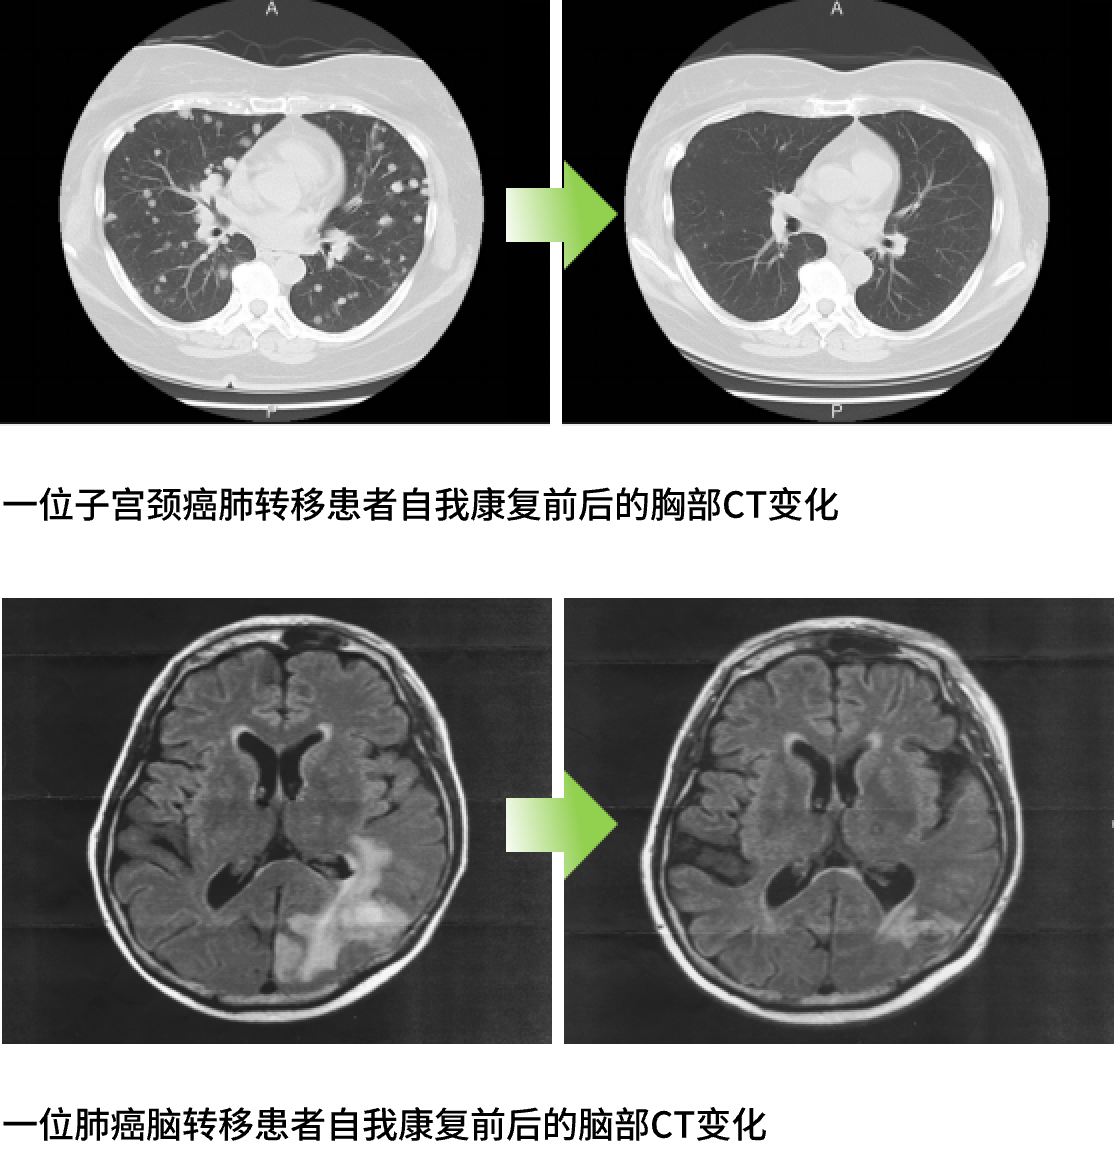

有很多癌症患者通过自助康复或者在治疗同时进行自助康复而实现了缓解(前者也被称为自然缓解)。这些患者身上有两大重要的共通之处:

所谓与癌共存,不代表不作为,它代表慢病治疗的思维。通过日常生活中的实践即自助康复来强化免疫力、线粒体活性和基因防御力,进而改变体质——将原来容易患癌体质调整为不易体质,从而实现与癌长期共存甚至治愈的目标。